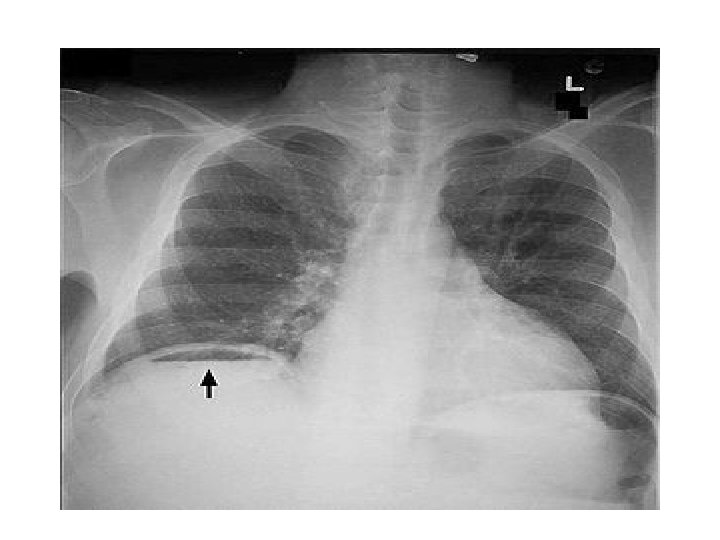

Pneumoperitoneum/ Air under the diaphragm • Erect Chest Xray • Pneumoperitoneum indicates a perforated viscous • Causes : perforated PUD(duodenal ulcer), ruptured appendicitis, typhoid perforation, necrotising enterocolitis, ruptured inflammatory bowel disease, ruptured diverticulitis, bowel cancer, penetrating trauma.